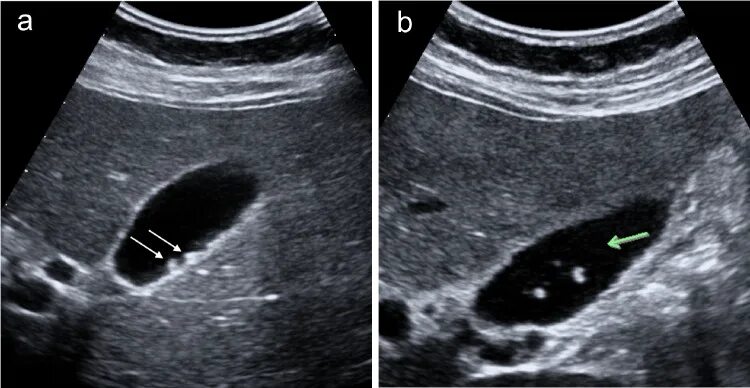

Удаление полипов желчного пузыря операция